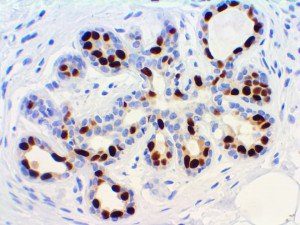

The first cytokines released are interleukin 1β (IL-1β) and tumor necrosis factor-α (TNF-α), which attract a variety of circulating white blood cells (WBCs) to the infection site, including neutrophils, monocytes, macrophages, and natural killer (NK) cells. This response, along with the antipathogenic chemicals released by these cells (i.e., complement), comprise the innate immune response. These cells directly attack the invading pathogen and also release additional cytokines, chief among them interleukin-1 and 6 (IL-6). IL-6 is essential for invoking the adaptive immune response, which calls T-cells, B-cells, and T helper (Th) cells to the infection site. IL-6 also stimulates further recruitment, proliferation and activation of macrophages.

It is the ICU physician who is most likely to witness one of the deadliest manifestations of the abnormal immunological response, the cytokine storm syndrome (CSS). This response is also referred to by some as the cytokine release syndrome (CRS). CSS is characterized by continuous activation and expansion of macrophage and lymphocyte populations, which secrete large amounts of cytokines, causing the cytokine storm. This massive cytokine release is akin to hemophagocytic lymphohistiocytosis (HLH) disease, a syndrome characterized by initial unchecked and persistent activation of cytotoxic T lymphocytes and NK cells.

Clinical and laboratory manifestations of HLH include fever, enlarged liver and/or spleen, neurologic dysfunction, coagulopathy, liver dysfunction, cytopenias (i.e., low levels of erythrocytes, leukocytes, and/or platelets), hypertriglyceridemia, hyperferritinemia, hemophagocytosis, and eventually diminished NK cell activity as the immune system becomes progressively paralyzed. HLH can be familial (primary HLH) or secondary to another disease process (sHLH), such as rheumatic disease, in which it is referred to as macrophage activation syndrome (MAS, characterized by elevated ferritin).